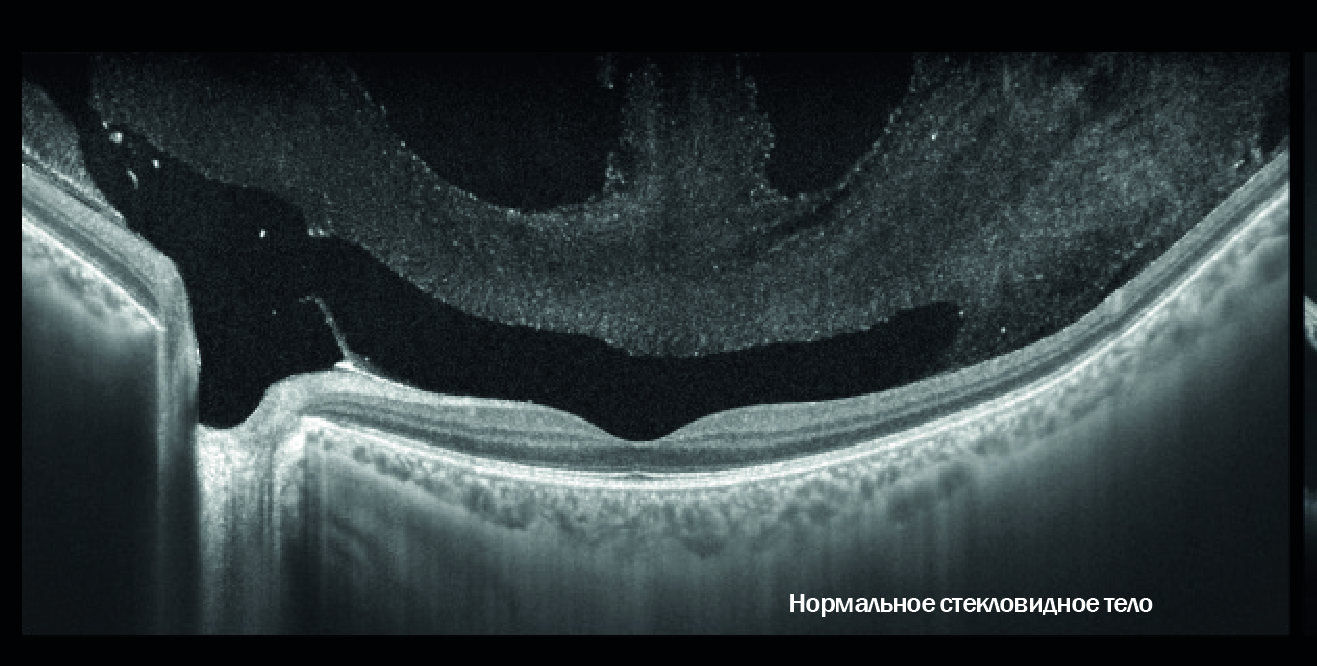

ОКТ Yalkaid использует для сканирования невидимый глазом свет с длиной волны 1060 нм. Свет с такими параметрами лучше проникает сквозь проводящие среды глазного яблока, что позволяет выполнять исследование у пациентов с катарактой и помутнением стекловидного тела. Невидимый глазом свет не отвлекает пациентов, поэтому создаются лучшие условия для получения детализированных снимков даже у детей и пожилых людей.

Широкое поле обзора и большая глубина сканирования | Отслойка сетчатки